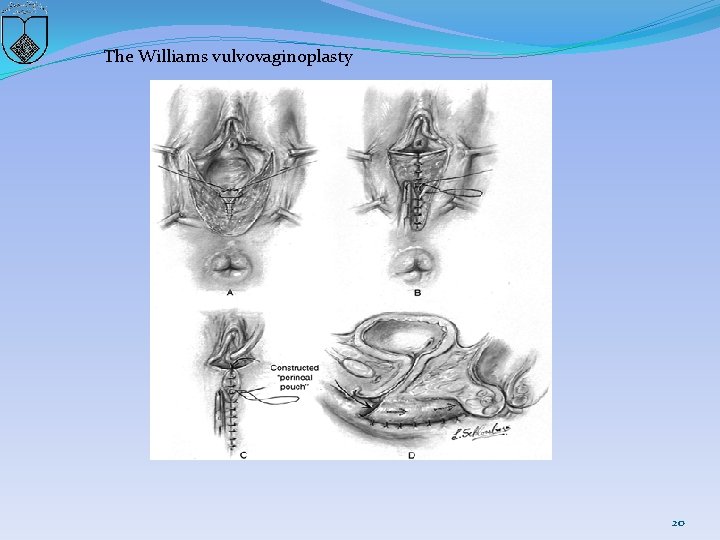

The Williams vulvovaginoplasty 20